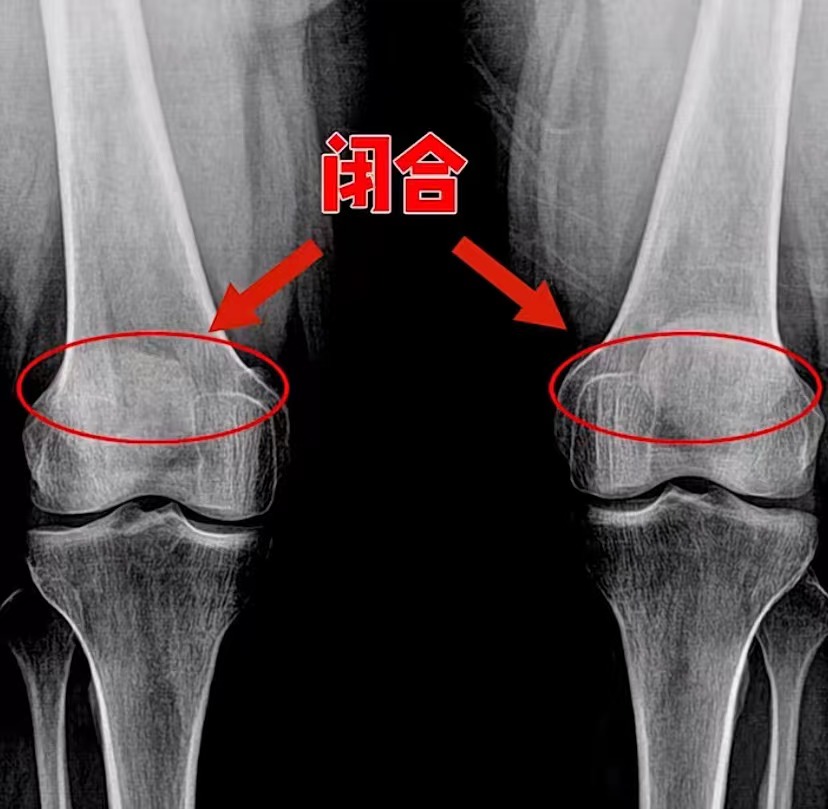

但是如果女孩骨龄14岁以上,骨骺线闭合;男孩骨龄16岁以上,骨骺线闭合,那是再没有机会长高了!